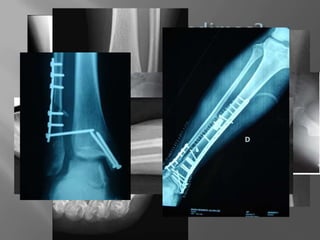

1. Abierta / Cerrada

Transversal  Oblicua  Espiroidea  Conminuta

1. Politraumatizado inestable hemodinamicamente  2. Compromiso neurovascular  3. Fractura de pelvis (*)  4. Fractura de hueso largo desplazada  5. Sección tendinosa  6. Síndrome compartimental